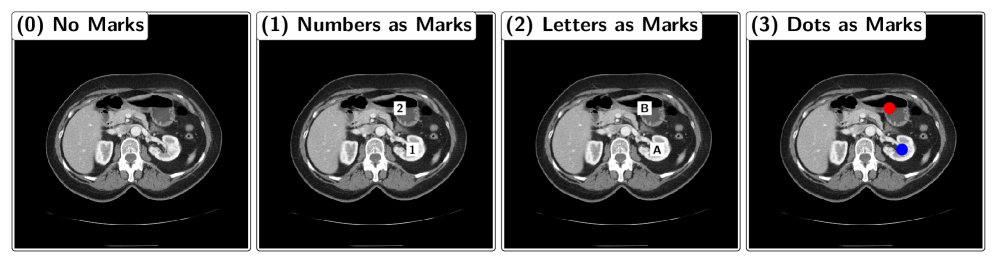

We introduce the MIRP Benchmark dataset to systematically evaluate VLMs’ ability to identify relative positions in medical images. The dataset consists of abdominal CT slices, each paired with a question about the relative position of two anatomical structures, following a standardized template: “Is the structure1 above/below/to the left of/to the right of the structure2?”. The slices are randomly rotated and flipped to ensure that the model must derive relative positions from the image rather than relying on anatomical priors to produce a correct answer. The MIRP dataset is balanced, with an equal distribution of yes and no answers to questions. The two anatomical structures referenced in the question are optionally highlighted with visual markers. Three marker types are evaluated: (1) black numbers in a white box, (2) black letters in a white box, and (3) a red and a blue dot (see Figure 2). The following sections describe the dataset generation process and the VLM evaluation pipeline. While these sections are not required to understand the experiments and results, they provide additional context for our study.

Refer to caption

Figure 2: Different visual markers. Note: The real marks are smaller as shown here.